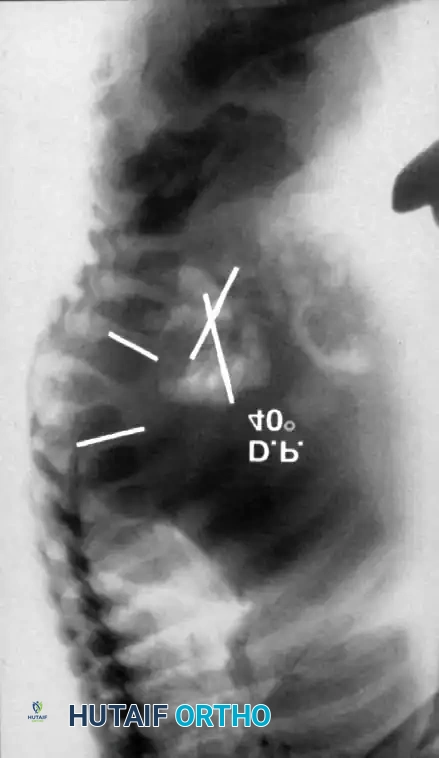

Two-year-old child with type I congenital kyphosis

Posterior column shortening A

Posterior column shortening B

Posterior column shortening C